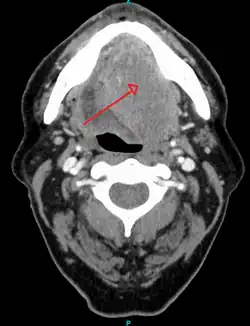

Risk factors include tobacco and alcohol use.[9][10] Those who use both alcohol and tobacco have a 15 times greater risk of oral cancer than those who use neither.[11] Other risk factors include betel nut chewing[12] and sun exposure on the lip.[13] HPV infection may play a limited role in some oral cavity cancers.[14] Oral cancer is a subgroup of head and neck cancers.[6] Diagnosis is made by sampling (biopsy) of the lesion, followed by an imaging workup (called staging) which can include CT scan, MRI, PET scan to determine the local extension of the tumor, and if the disease has spread to distant parts of the body.

After the tissue is confirmed cancerous, other tests will be completed to:

- better assess the size of the lesion (CT scan, MRI or PET scan with 18F-fluorodeoxyglucose (FDG)),[45]: 143

- spread to the lymph nodes (CT scan) or